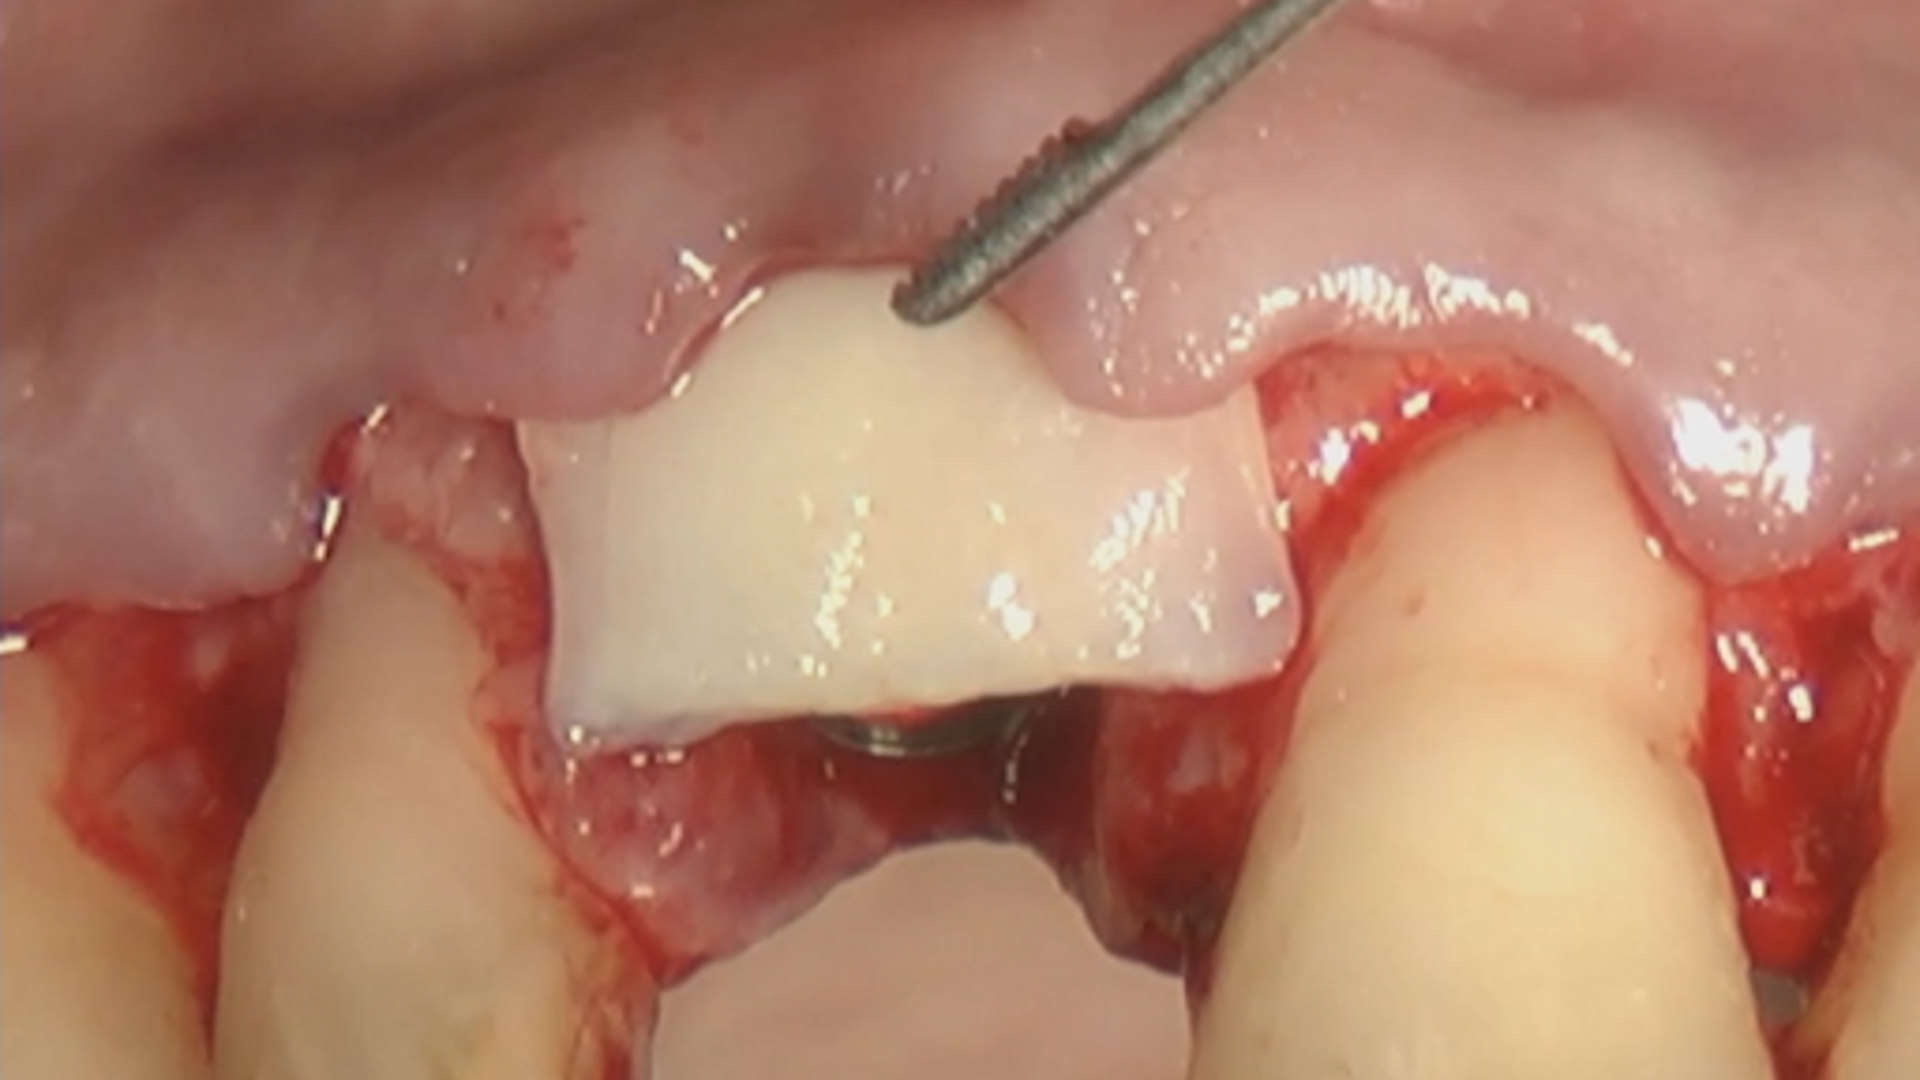

2nd ReLIVE Surgery - Soft tissue augmentation for a guided implant placement at the level of lateral incisor

Hands-On Video Part 2 - Site-specific preparation for a guided implant placement

Hands-On Video Part 3 - Connective tissue graft harvesting and disepithelisation